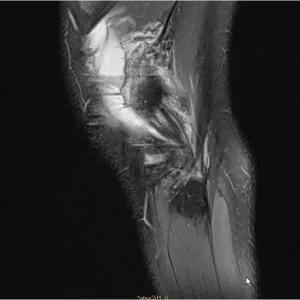

Josep Maria Muñoz-Vives presents the case of a 43-year-old male who sustained polytrauma as a result of a climbing accident... The goals of this clinical case are to discuss the management, classifications and sequelae of pelvic fractures.